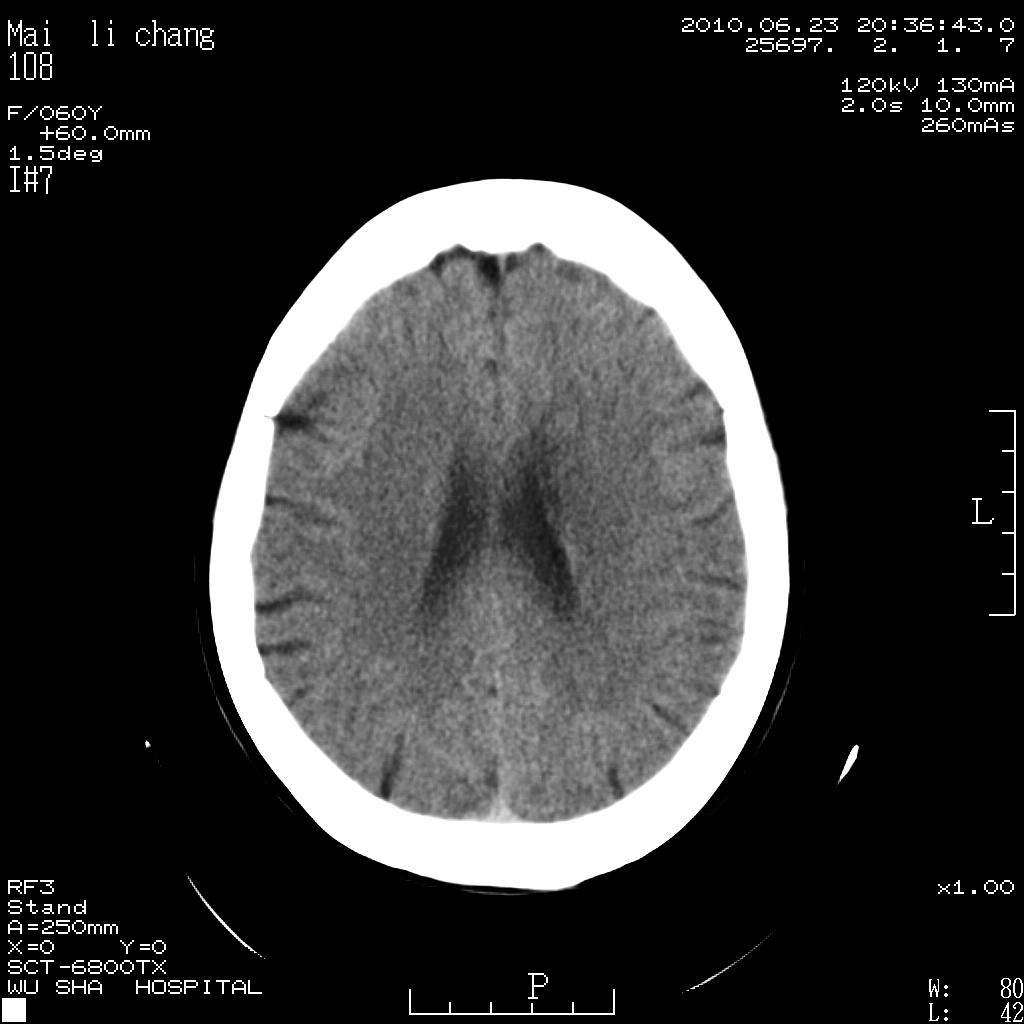

女性,60岁,右手无力一天

脑梗塞?并皮层下动脉硬化性脑病?还需要考虑什么?请大家指导,先谢了。

左侧基底节区及放射冠区多发脑梗塞。

左侧基底节区及侧脑室旁多发脑梗塞

2.左侧基底节区可见片状低密度病灶。

意见考虑脑梗塞。

左侧基底节区大面积梗塞,必要增强扫描协诊

左侧基底节及放射冠区脑梗塞。